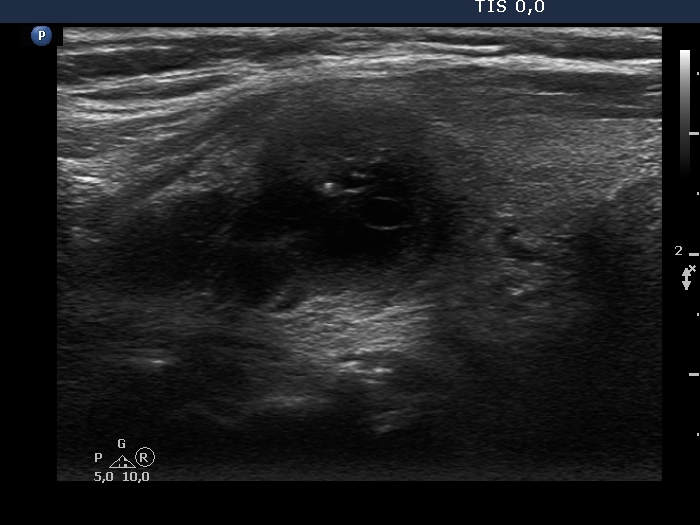

Ultrasonography. The thyroid was echonormal. There was a mixed moderately hypoechogenic-cystic nodule in the right lobe. The lesion presented various intranodular hyperechogenic granules including back wall figures, non-specific granules and a few typical comet-tail artifacts. There were other, difficult-to-classify bright granules. The latter could be either comet-tail artifacts or microcalcifications. There were several moderately hypoechogenic lesions in the left lobe.

Comments. This case illustrates the difficulty of distinguishing comet-tail artifact from microcalcification. The relevance of this differentiation lies in the consequences, the former is found almost always in benign lesions while the presence of microcalcifications increases the likelihood of papillary carcinoma.